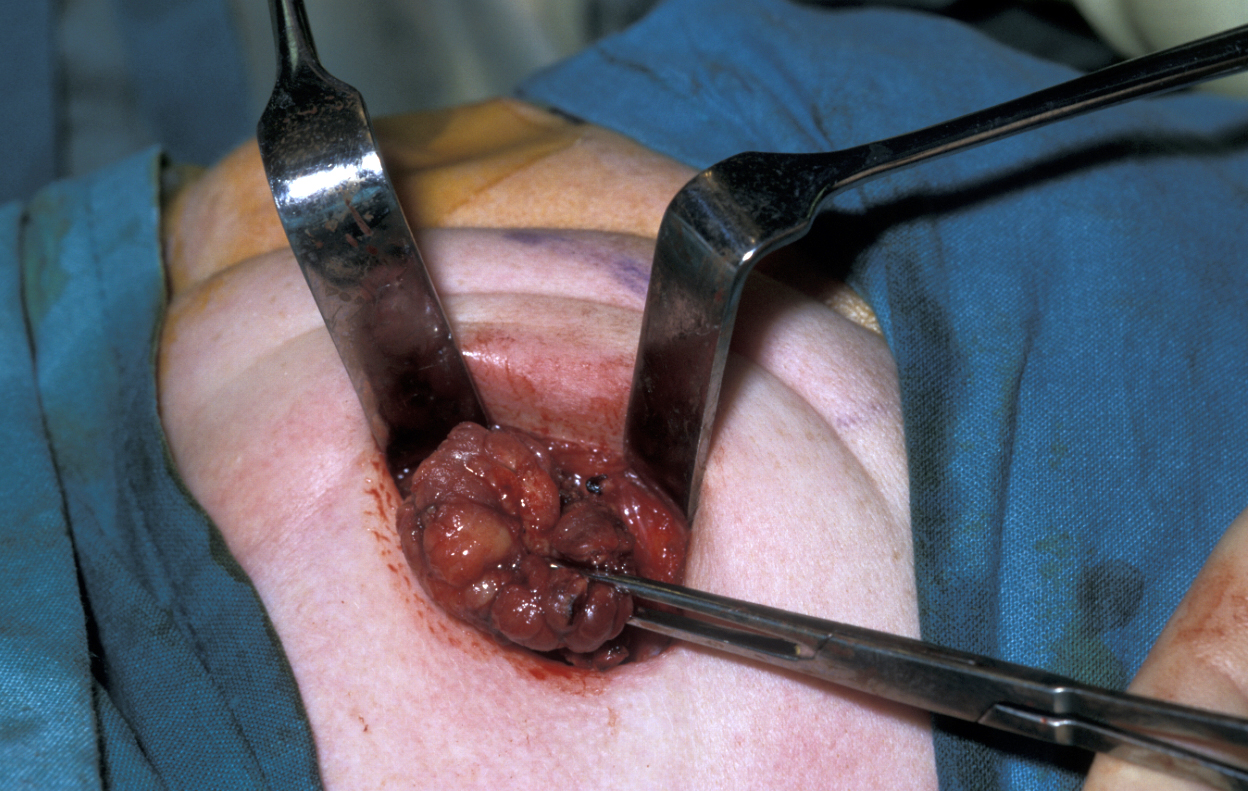

Another location where salivary gland pleomorphic adenoma may occur is in the palate area, most often at the junction of hard and soft palates (see Figure 7).

Figure 7: Palatal pleomorphic adenoma arising at a typical site.

Figure 8: Excision of palatal pleomorphic adenoma by using a cleft palate gag to aid access. Subperiosteal stripping provides an adequate margin and heals well by allowing simple granulation to occur.

For all tumours which overlay the hard palate, simple subperiosteal excision with a mucosal margin is adequate (see Figure 8). Healing by secondary intention (leaving the wound as is) of the palate is excellent and can be achieved by using a dressing plate with a sedative and soothing dressing. If the tumour extends into the soft palate, the capsule of the tumour can be elevated from the underlying levator aponeurosis (a thin structure that connects the levator muscle (the muscle responsible for lifting up the soft palate when saying ‘ahhh’) . The soft palate defect will granulate with good functional result. If the levator aponeurosis is breached, however, this has to be repaired and should be reconstituted with vascularised tissue, such as a buccal fat pad flap, or a temporoparietal fascial flap.